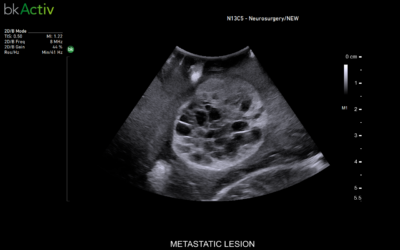

NÝTT ÓMTÆKI BKACTIV

Bk medical hefur sett á markaðinn nýtt ómtæki bkActive til...